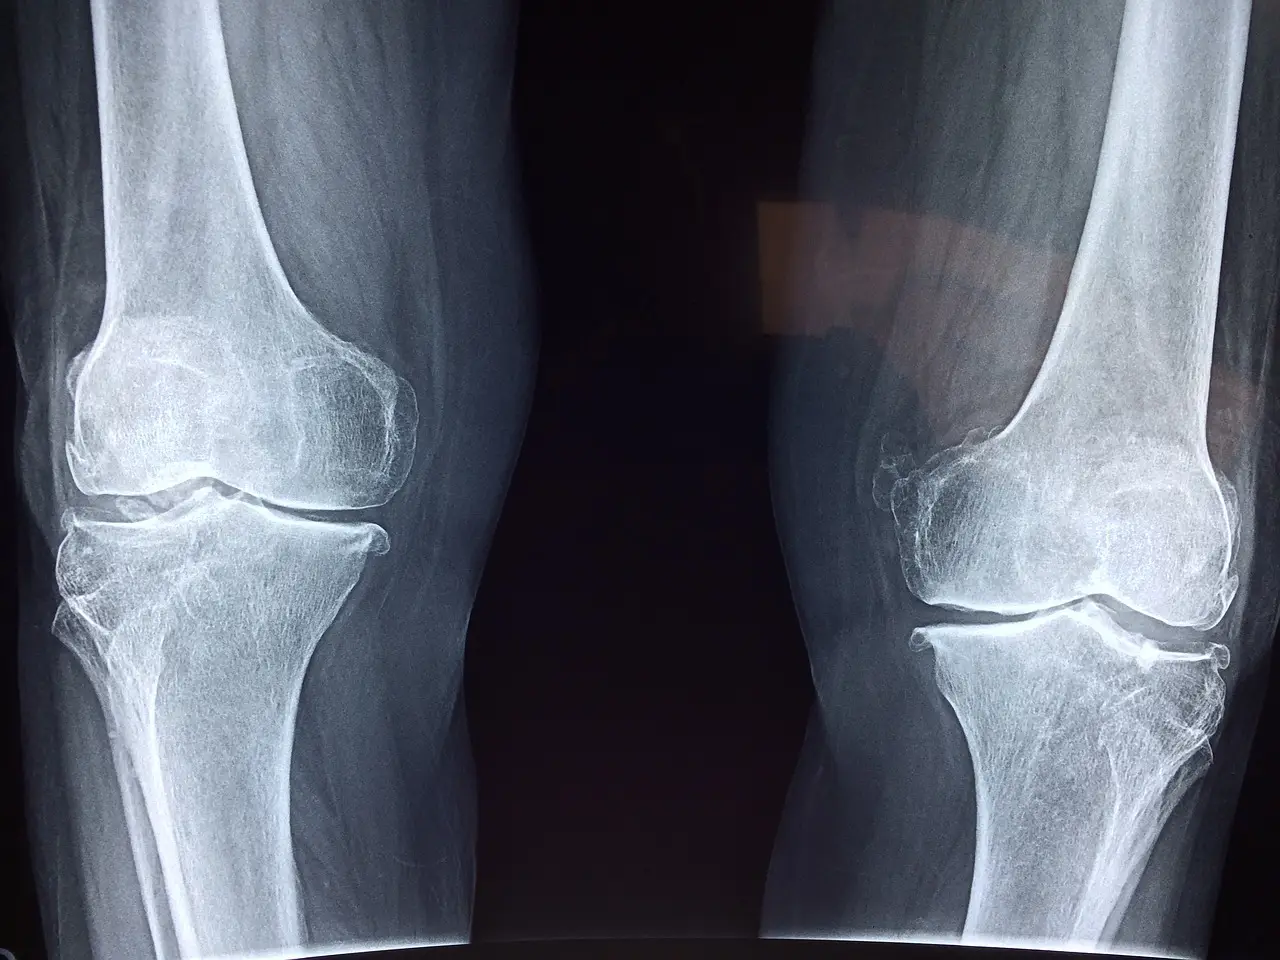

첫째, 콘드로이친은 관절과 연골을 보호하는데 이러한 연골은 뼈 사이에서 마찰을 줄이고 충격을 흡수하는 역할을 합니다.

둘째, 콘드로이친은 관절 건강에 도움이 되므로 노화나 관절 질환으로 인한 연골의 퇴행을 지연시킬 수 있습니다.

셋째, 콘드로이친은 연골 보호와 재생 능력에 도움이 되어 관절 통증을 감소시켜 관절 기능을 개선할 수 있습니다.

넷째, 콘드로이친은 연골 손상을 예방하여 운동선수나 연골 문제에 위험성이 있는 사람들에게 도움이 될 수 있습니다.